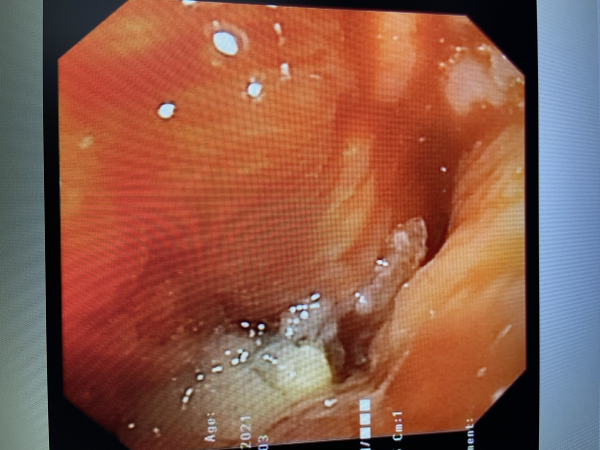

2021年3月4日,阳新患者石某因胸闷气短在当地卫生院治疗效果不佳,来我院呼吸内科门诊就诊,经胸部CT检查发现右肺肿瘤。于是3月5日收入院行无痛支气管镜检查提示:患者右主支气管因肿瘤浸润生长后导致严重狭窄,肺活检送病理提示肺鳞癌。

患者右主支气管因肿瘤浸润生长后导致严重狭窄